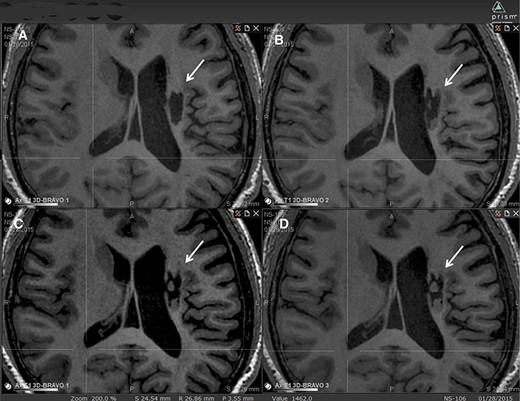

圖2:腔內組織生長的縱向MRI示例。

圖中顯示了B組 (#106) 受試者在T1MRI上隨時間的變化。

(A):基線時,(B) 6個月隨訪時,(C) 12個月隨訪時,(D) 24個月隨訪時。箭頭表示梗塞腔。

可以看到兩個組織團塊,在基線時不存在,推測是來自植入的NSI-566,隨著時間的推移,它們似乎慢慢填滿了腔體。